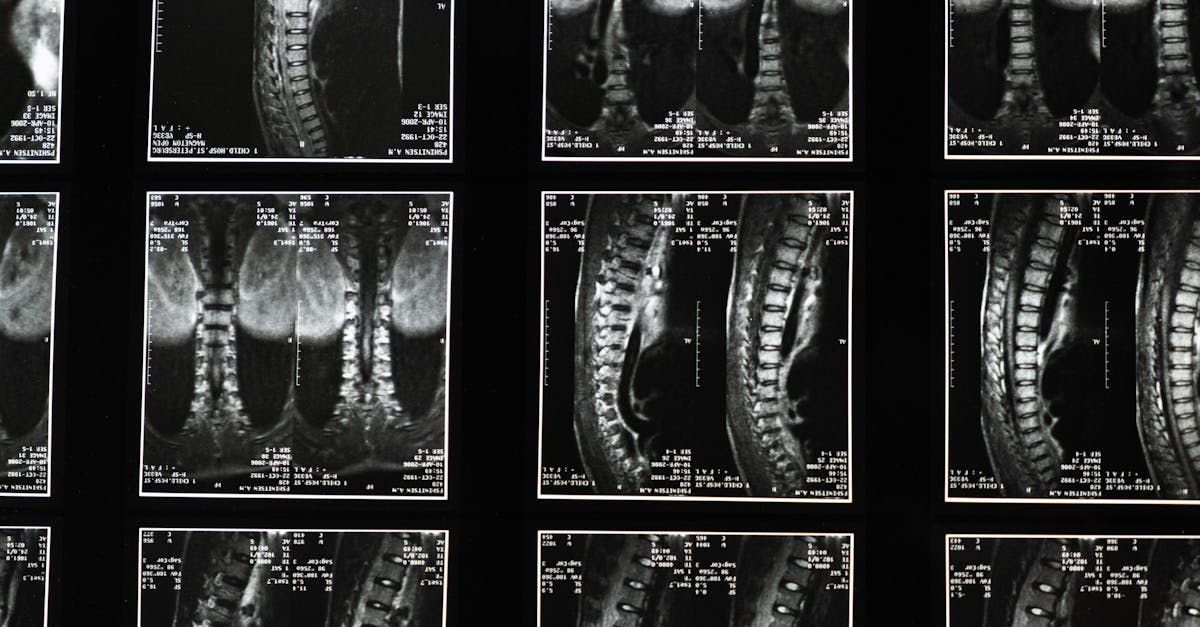

La décompression neurovertébrale est une technique non invasive qui utilise des appareils spécifiques pour exercer une traction contrôlée sur la colonne vertébrale. Cette méthode permet d’augmenter l’espace entre les vertèbres, ce qui réduit la pression sur les disques intervertébraux. Cela est crucial pour les personnes souffrant de hernies discales ou de douleurs chroniques dans le bas du dos. En libérant les nerfs comprimés et en améliorant la circulation sanguine, les patients peuvent ressentir un soulagement significatif de leur douleur.

Au cœur de cette approche se trouve le principe qui repose sur un processus de traction contrôlée appliqué à la colonne vertébrale. Ce traitement crée un espace entre les vertèbres, ce qui aide à réduire la compression sur les nerfs et favorise la circulation sanguine dans la région touchée. En améliorant l’apport en nutriments et en oxygène aux disques intervertébraux, la décompression neurovertébrale facilite la régénération des tissus, offrant ainsi un environnement propice à la guérison.